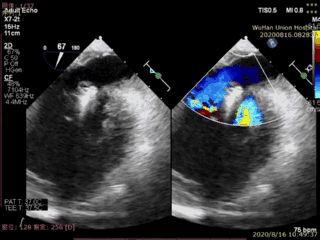

本例患者是一名高龄男性,合并多种疾病,术前超声心动图显示二尖瓣后叶P2脱垂、连枷伴重度二尖瓣反流。手术在食道超声引导下进行,植入1枚IIIs型二尖瓣夹合器,术后即刻显示二尖瓣反流消失,导管操作时间不到20分钟,手术取得圆满成功。

术后超声图